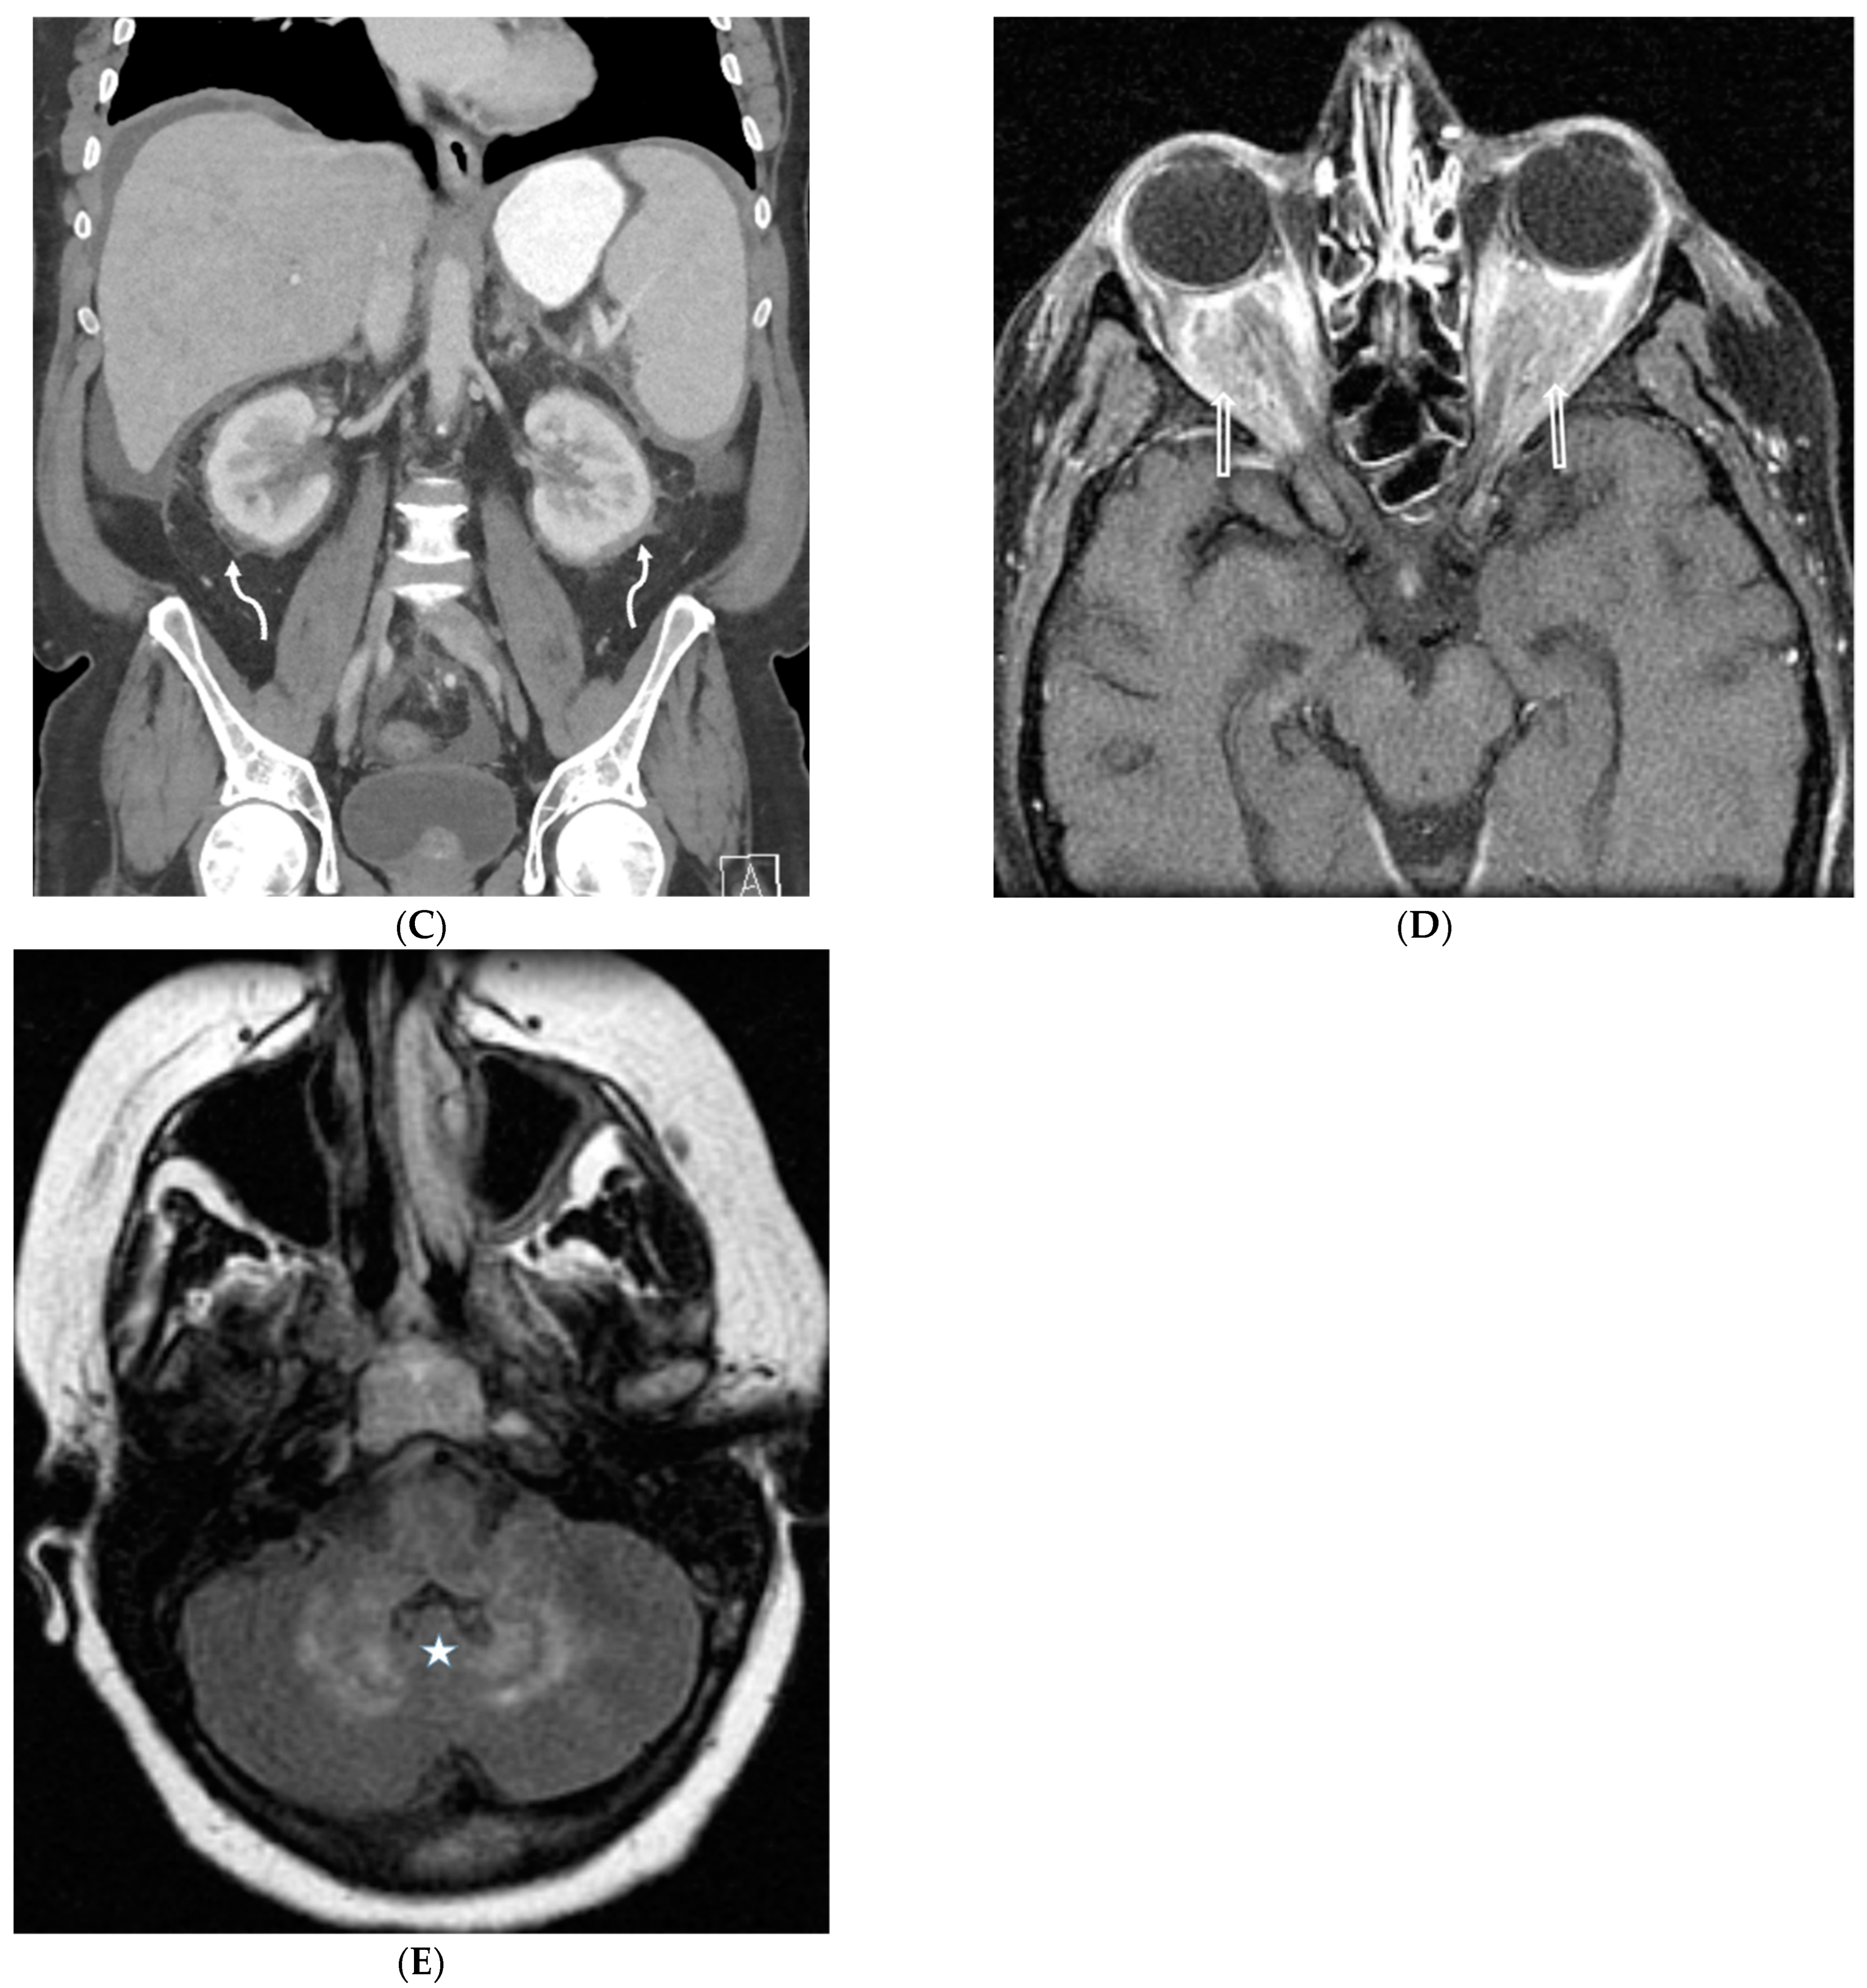

5.2. Kaposi’s Sarcoma

5.3. Lymphoma

5.4. Leukemia

8.2. Granulomatous–Lymphocytic Interstitial Lung Disease (GLILD)

8.3. Granulomatosis with Polyangiitis (GPA)

8.4. Erdheim Chester Disease (ECD)

8.5. Niemann–Pick Disease (NPD)